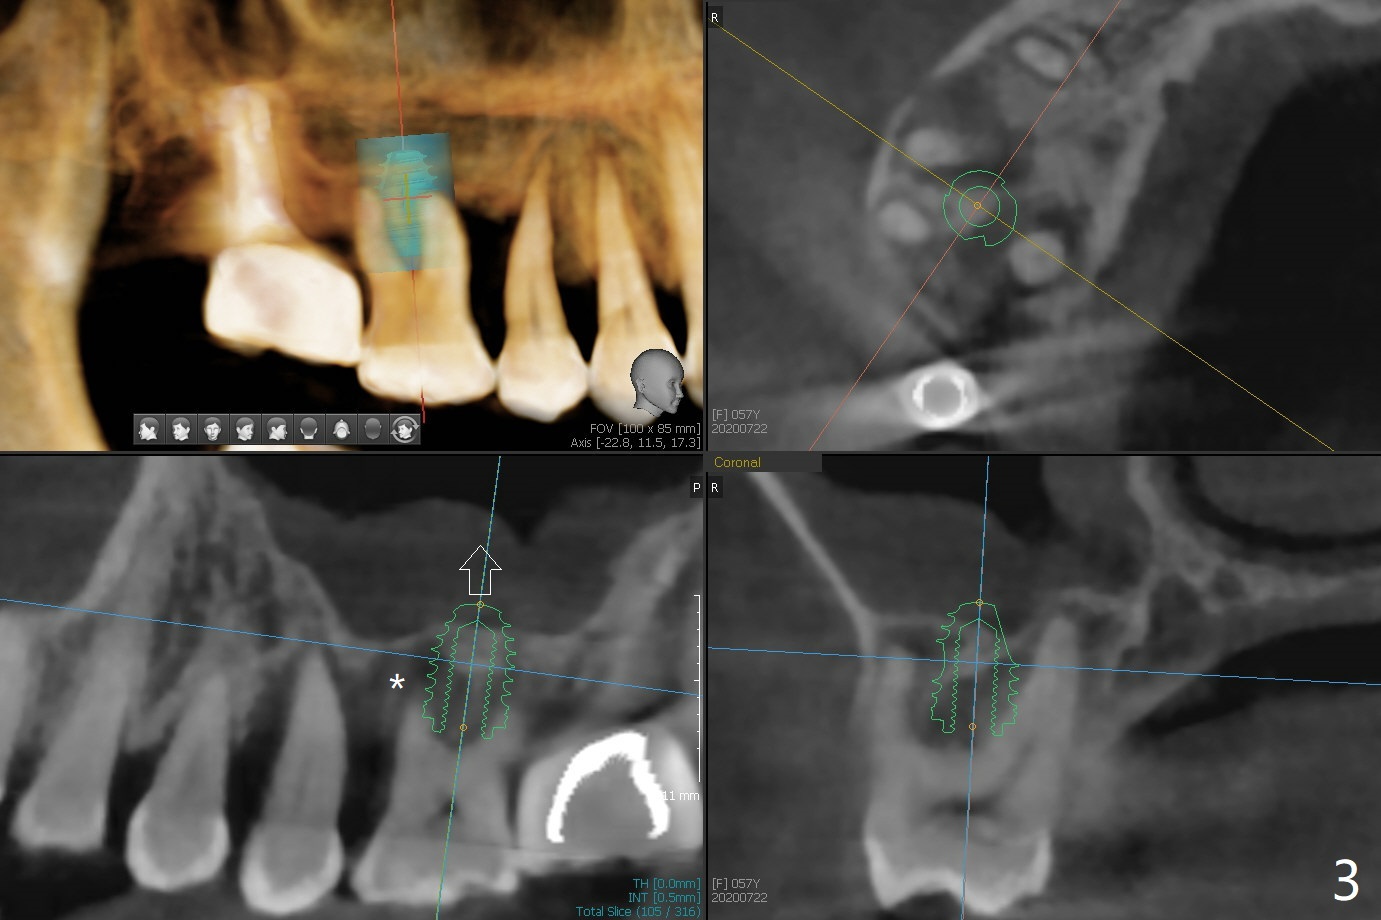

57岁女严重牙周炎,主诉右上磨牙食物堵塞(图一:圆圈)。第一磨牙骨质吸收,松动,需要拔除,尽管骨壁2-3毫米(图二),使用导航应该能取得5乘7.3毫米植体(图三绿色)初步稳定性。上颌窦膜厚,提升术不容易破裂,使用PRF膜预防及修补。由于近中骨质缺损严重(图三 *),植体可以再提高些(箭头),利用粘性骨做提升以及骨质缺损充填,似乎颊侧骨质多些(图五),植体可以小些,万一不行,就做提升和植骨。左上磨牙区骨壁更薄(图四,约1毫米),外提升术之后再种植。